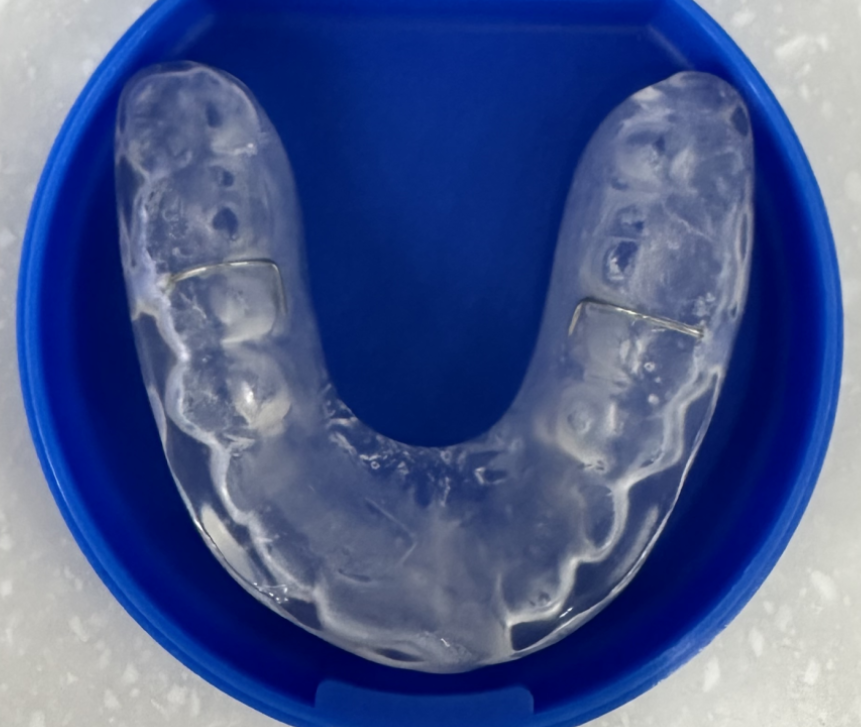

턱관절이 많이 안좋으면 장치를 껴야할 수도 있으니까요ㅠㅠ

증상에 따라 약 처방, 보톡스, 물리치료, 장치 치료